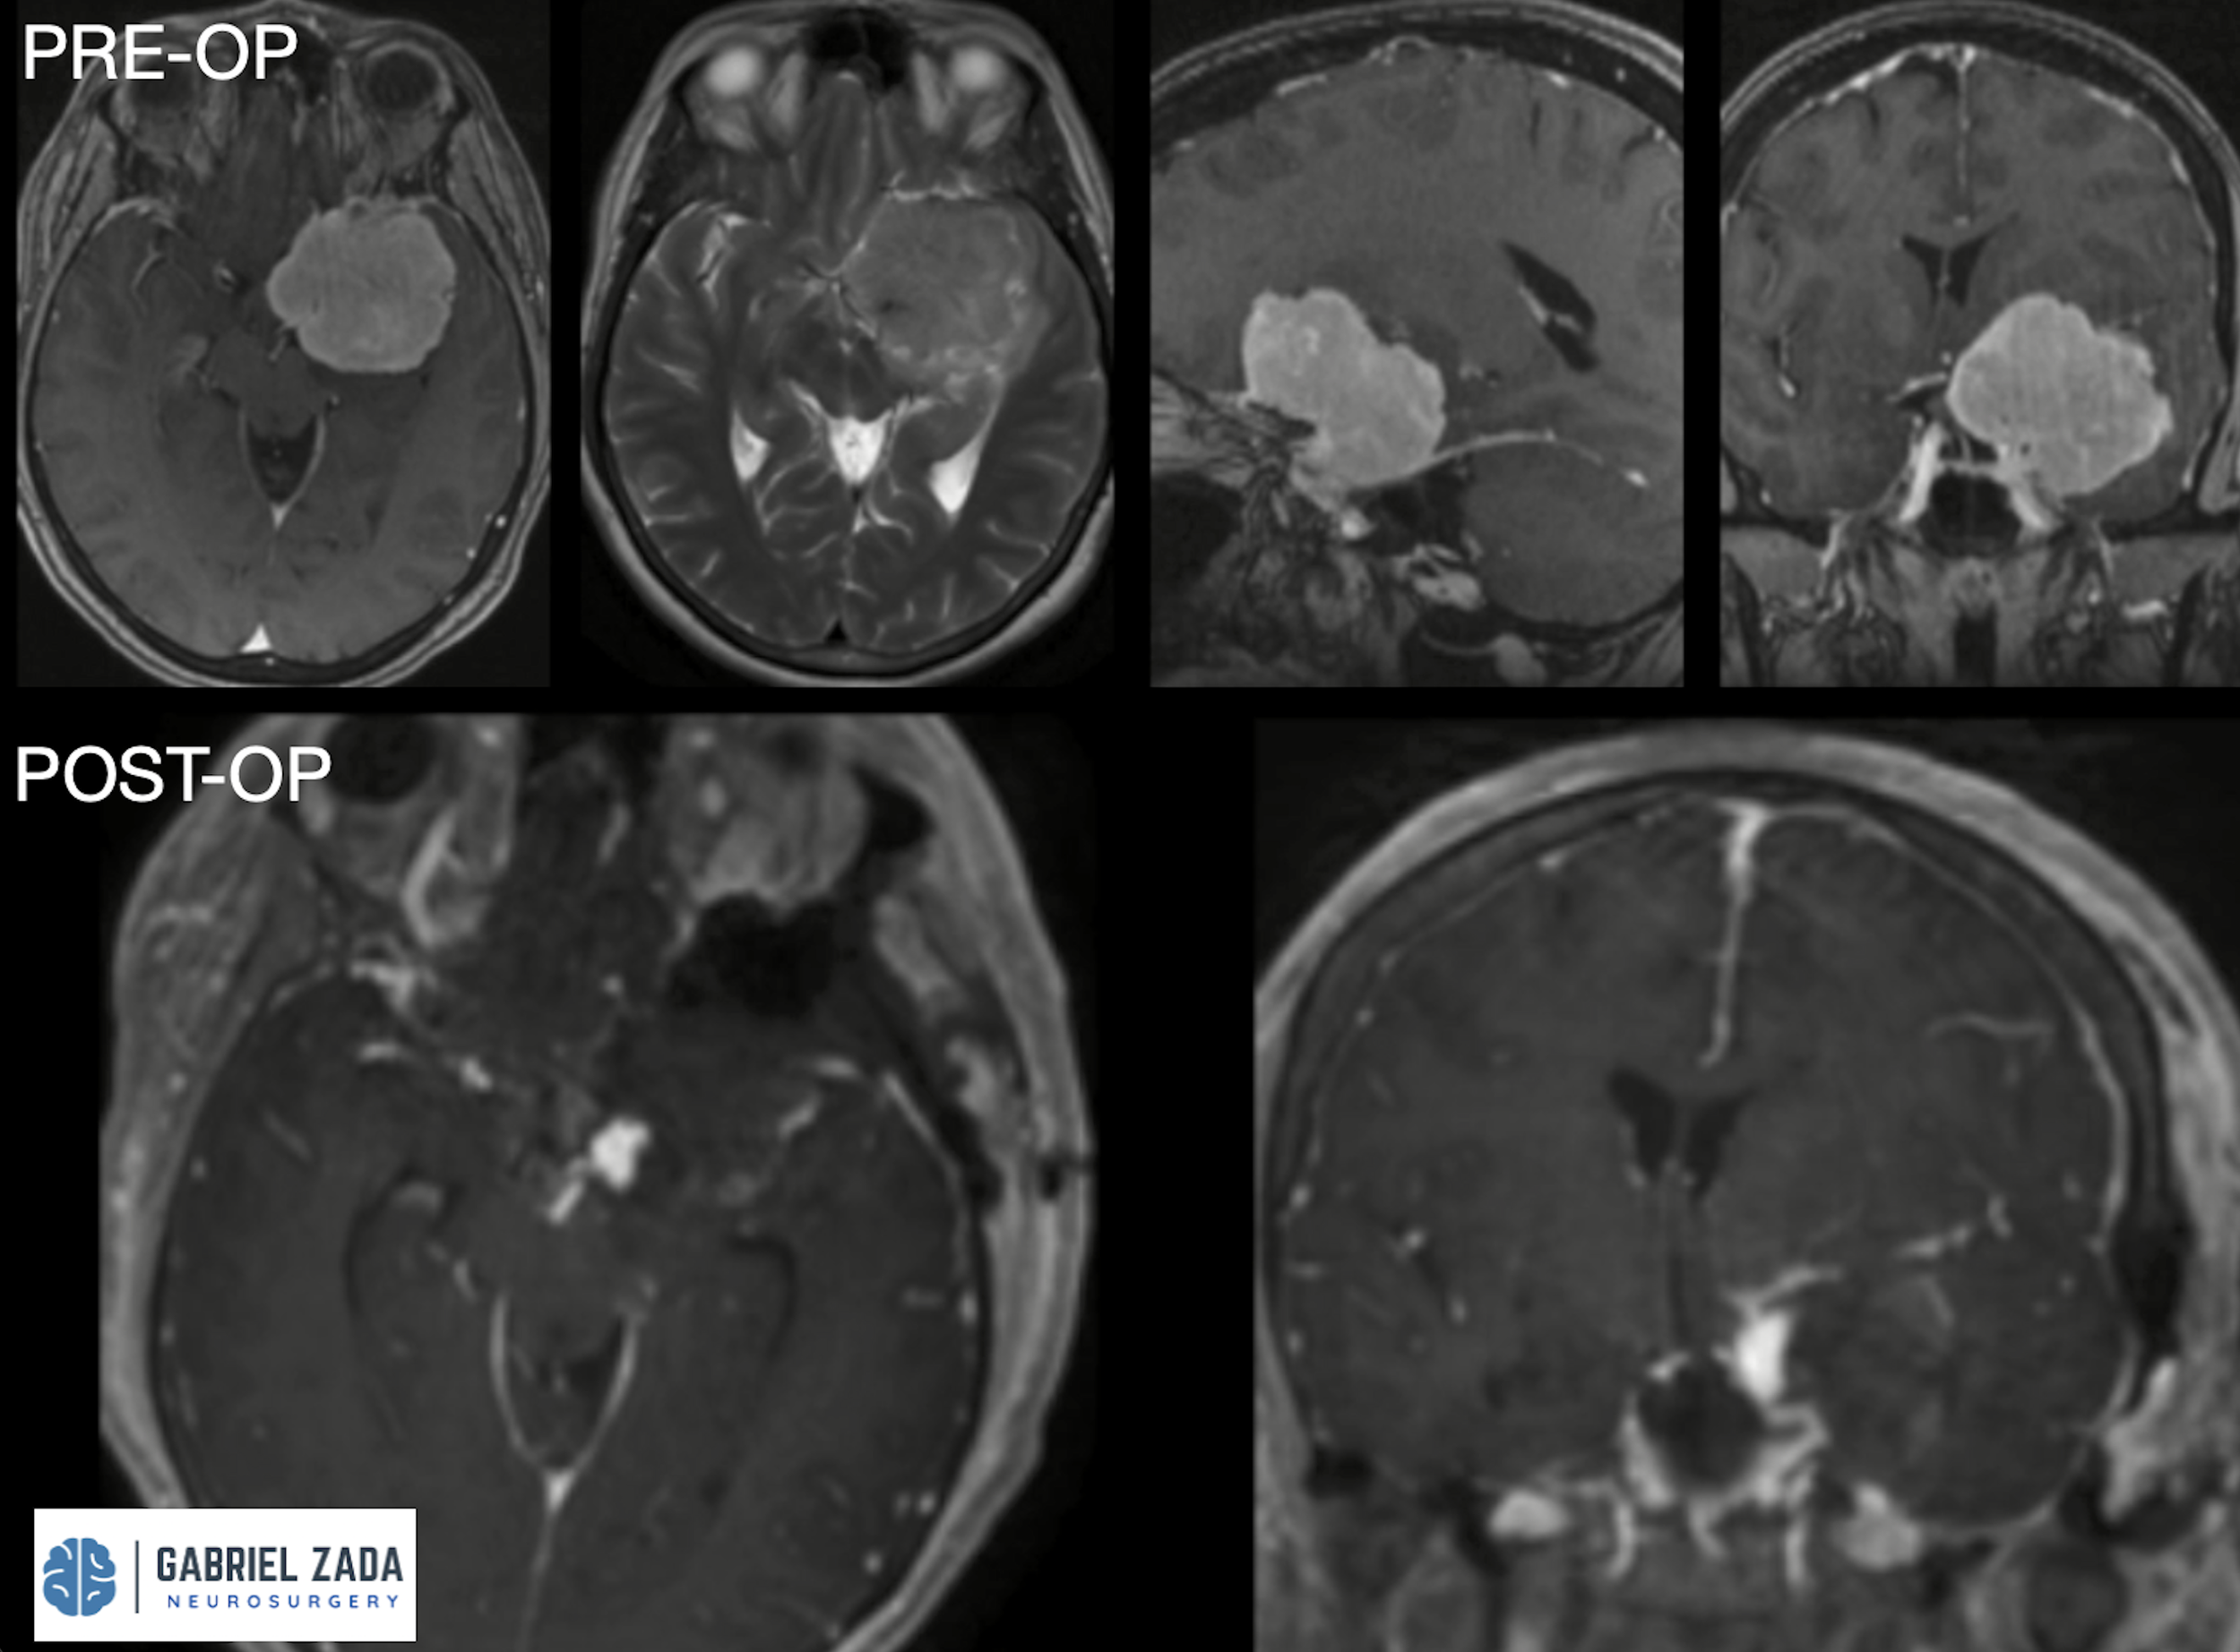

Explore this comprehensive gallery featuring pre‑ and post‑operative imaging of patients with skull‑base tumors treated by Gabriel Zada, MD, MS, FAANS, FACS. These cases highlight Dr. Zada’s expertise in advanced neurosurgical techniques and outcomes.

*Representative cases shown for educational purposes. All images de-identified. Individual results vary.